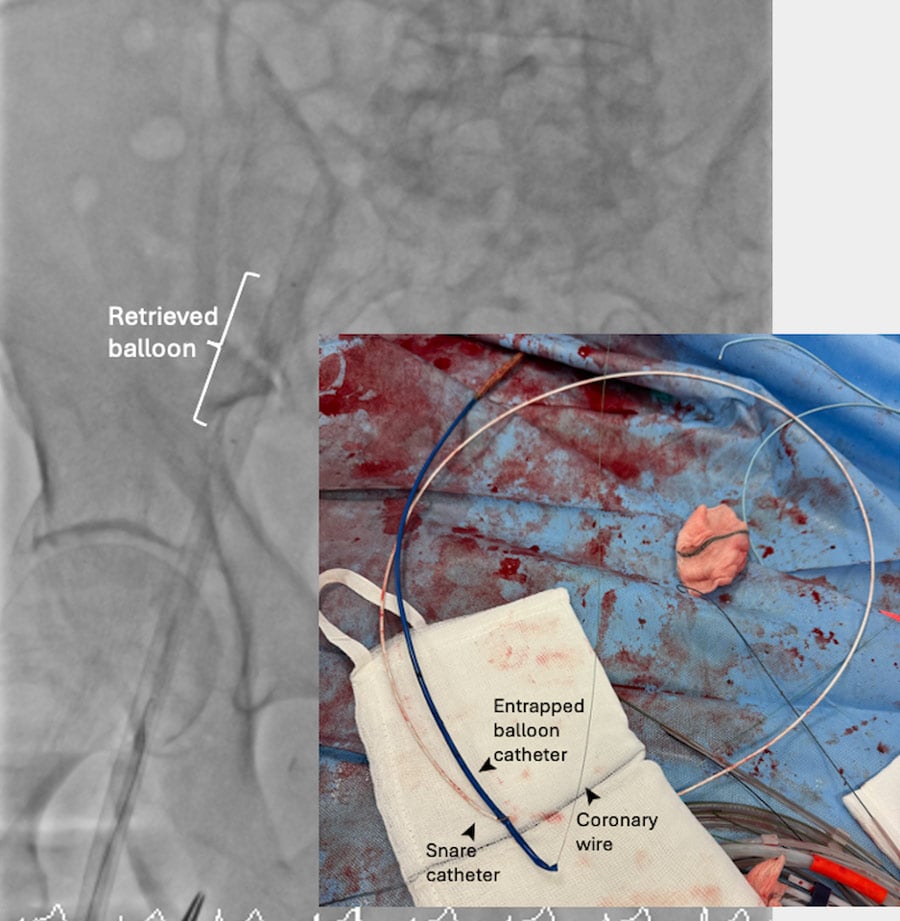

Once this was achieved, internal anchoring with a 2-mm balloon inflated within the wire lumen of the transected valvuloplasty balloon and ipsilateral snaring with a 5-mm Amplatz Goose SnareTM (Medtronic) straightened the system and allowed successful retrieval of the balloon (Figure 1E, Figure 1F, Moving image 3).

Figure 1E: Ipsilateral snaring and 2-mm balloon anchoring in central lumen of transected balloon.

Figure 1F: Successful retrieval of entrapped balloon.